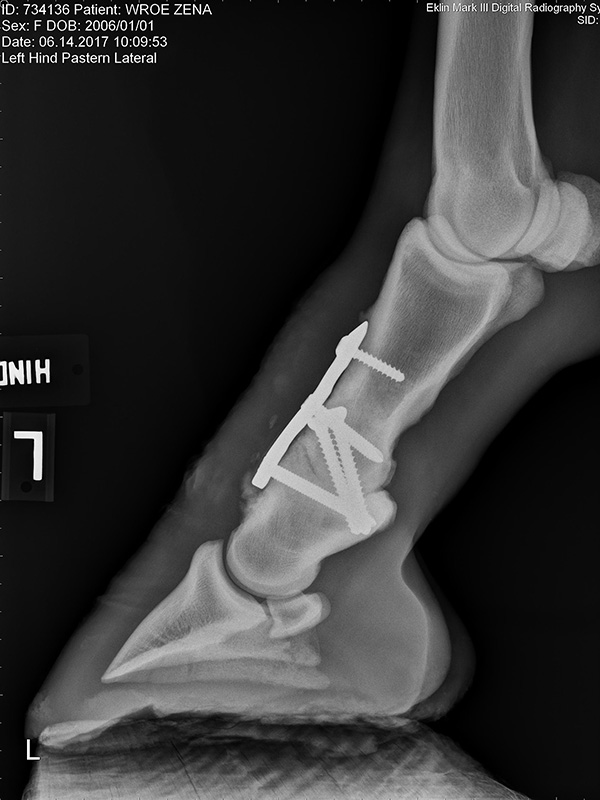

Prior to the study’s publication, Watkins had begun investigating a modified technique for arthrodesis of the pastern joint. That technique accomplished proximal interphalangeal (PIP) joint arthrodesis using a dorsally placed dynamic compression plate (DCP) in conjunction with two abaxially placed 5.5 mm cortex screws applied in lag fashion across the joint. The technique has continued to evolve over the years and today is usually performed using a locking compression plate (LCP) rather than a DCP. In Zena’s case, during her surgery in March of 2017, the pastern joint was exposed, all remaining articular cartilage was removed, the joint was realigned to its normal anatomical position, and a 3-hole LCP interphalangeal plate (PIP plate) was applied in conjunction with transarticular, 5.5 mm cortex screws placed in lag fashion. The PIP plate, a special purpose 3-hole locking compression plate, was designed by the AO Technical Commission’s Veterinary Expert Group (VEEG), specifically for this purpose. Watkins was chairperson of the VEEG at the time the PIP was developed.